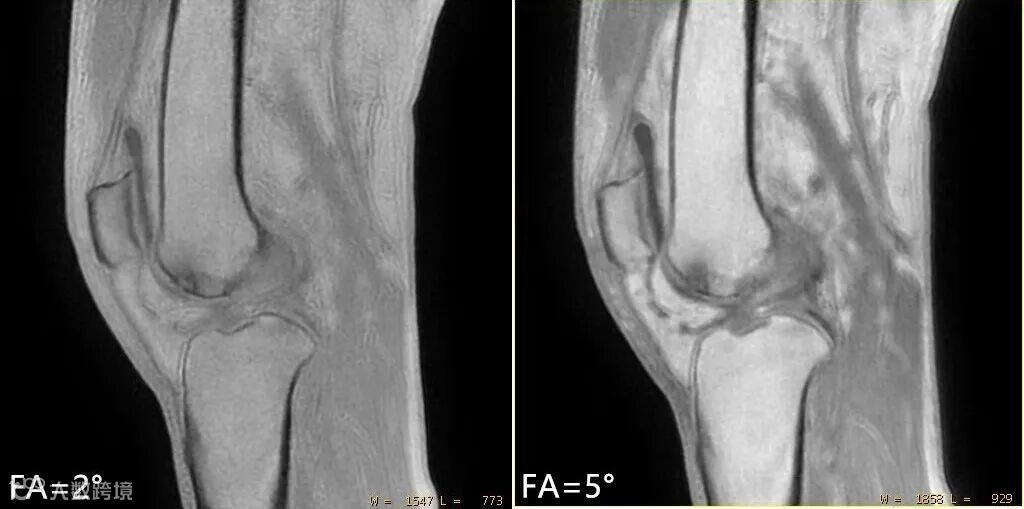

翻转角FA:FA越大,信噪比越高,但随着FA的增加骨质与周围软组织对比度会变差,如下图▽。